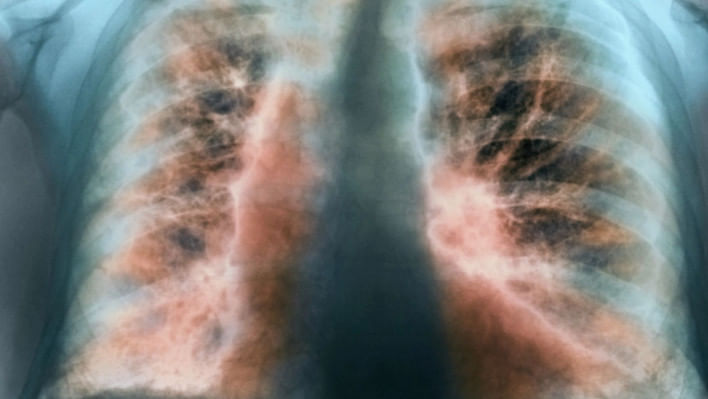

আইপিএফ

কোন রোগে ভুগছিলেন ওস্তাদ জাকির হোসেন, কেন হয়, কাদের হয়